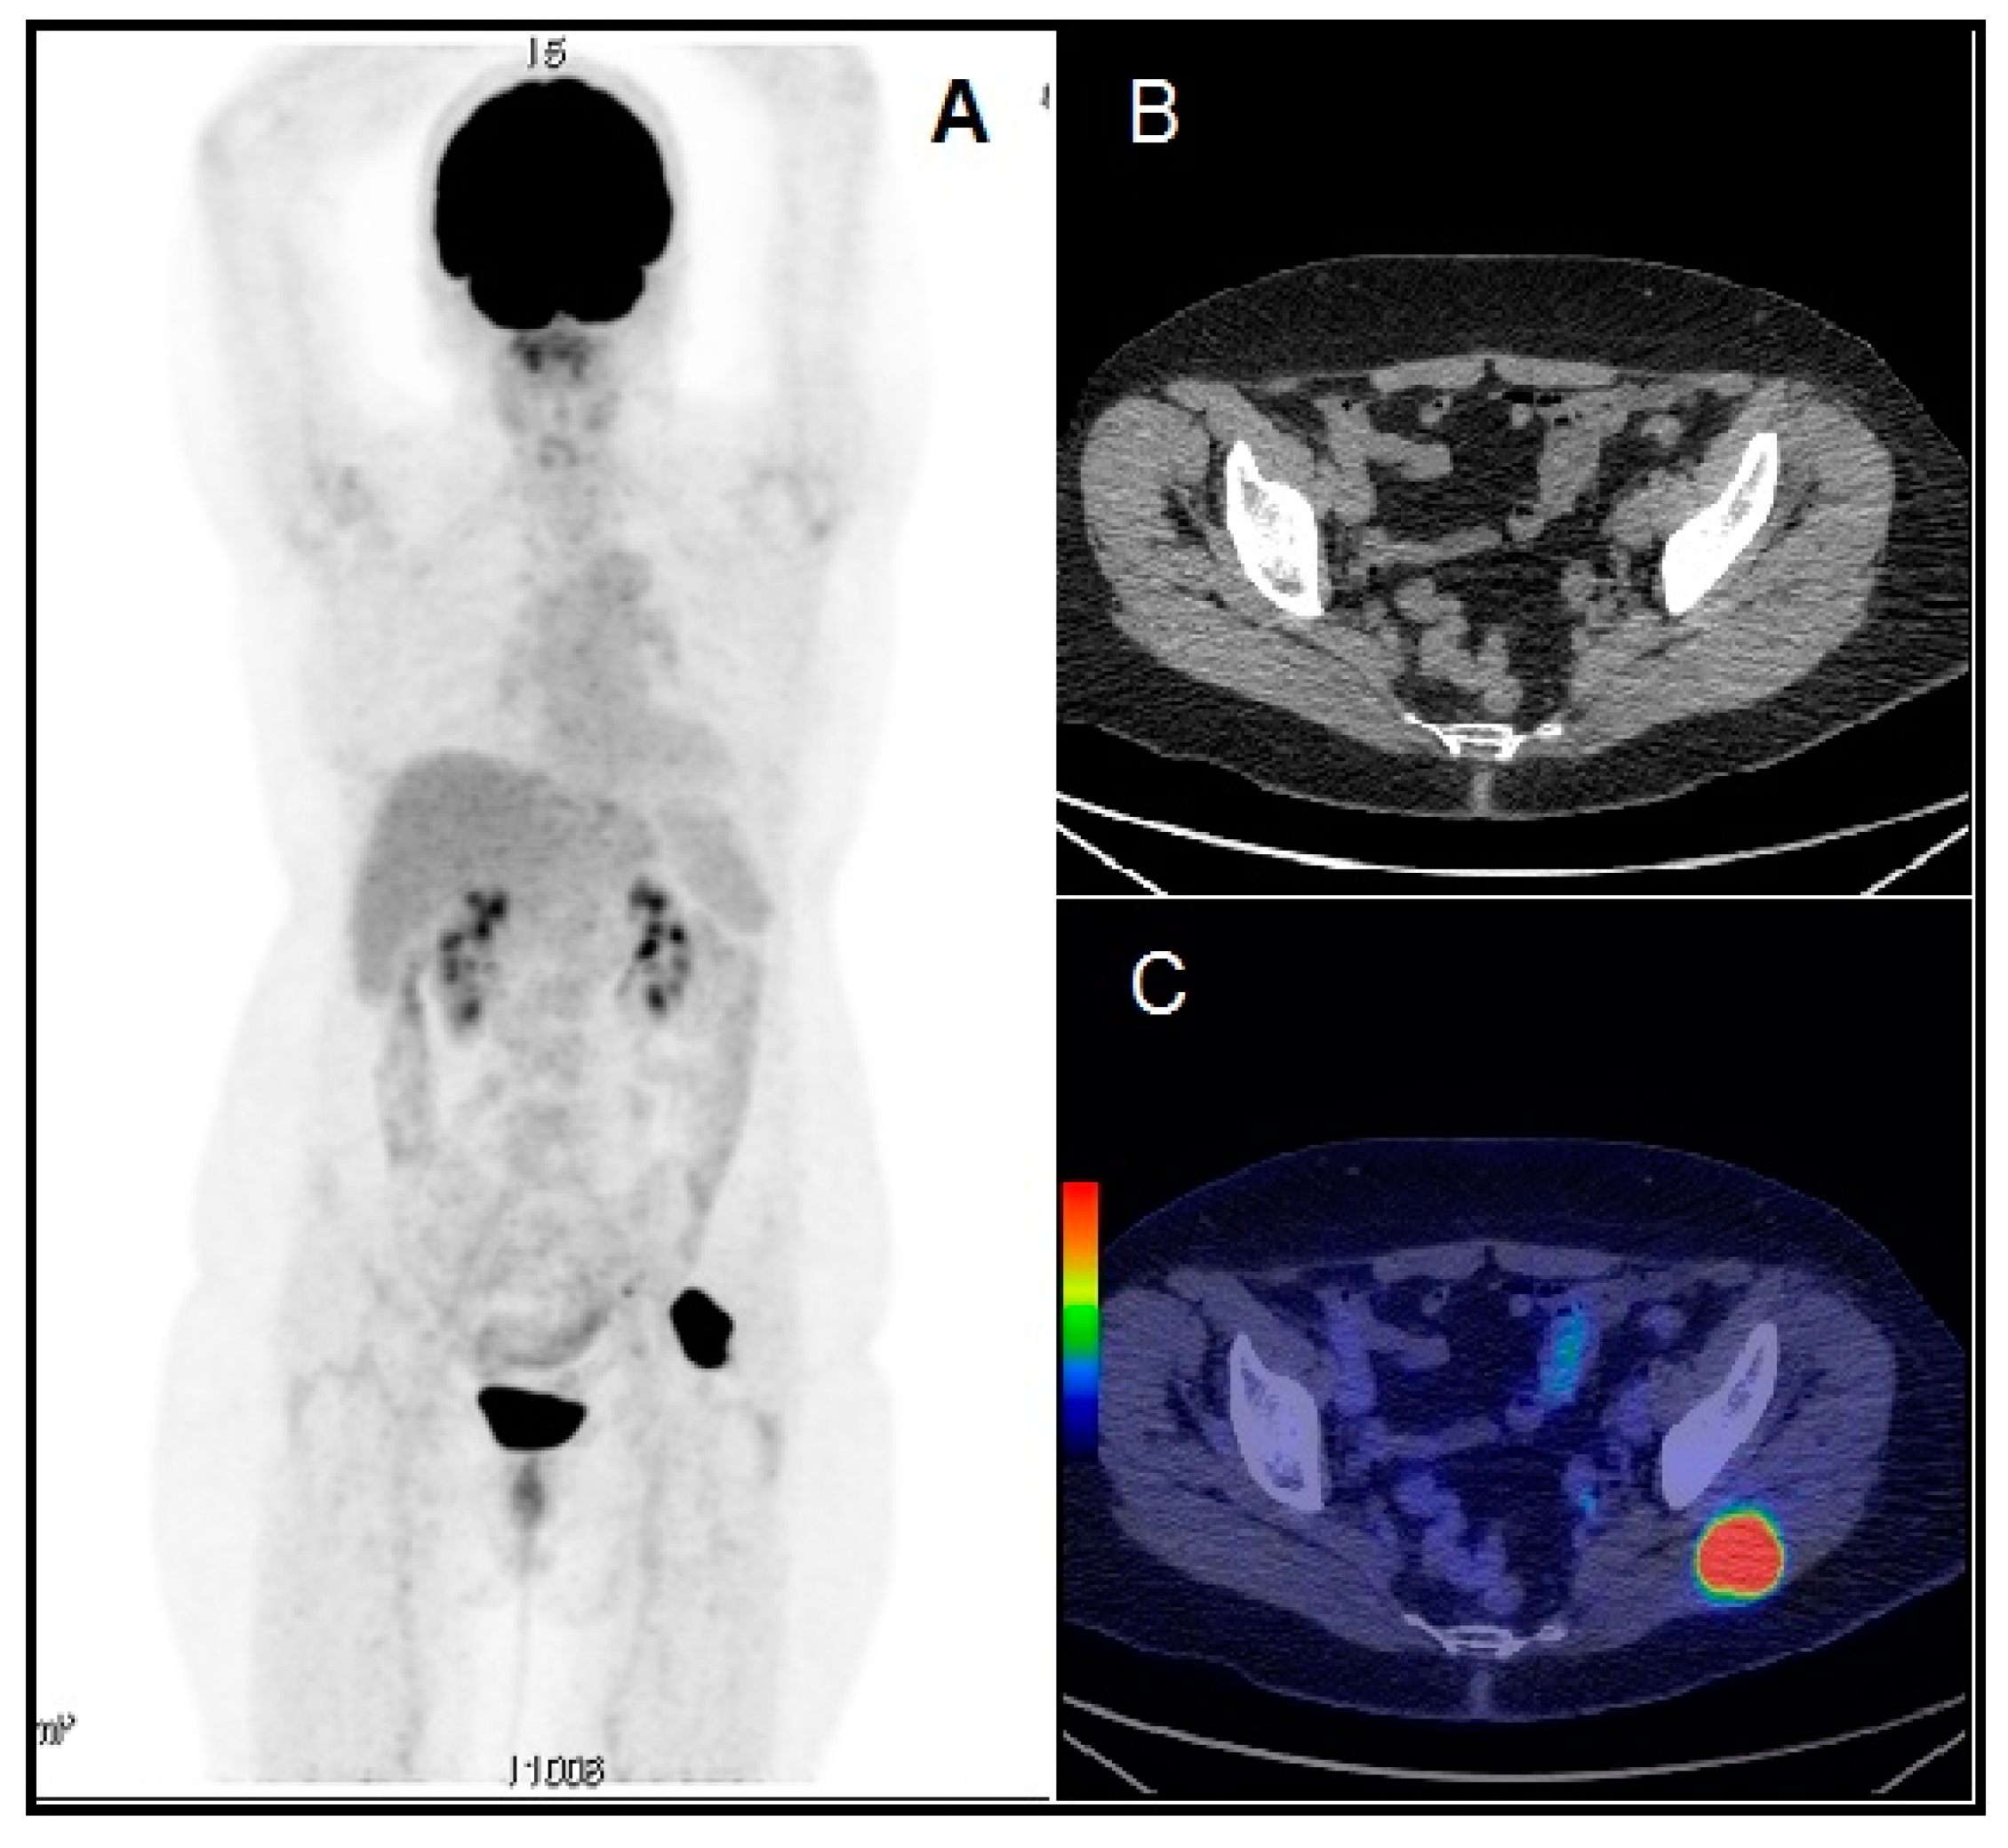

Skeletal Muscle Metastasis in Papillary Thyroid Microcarcinoma Evaluated by F18-FDG PET/CT